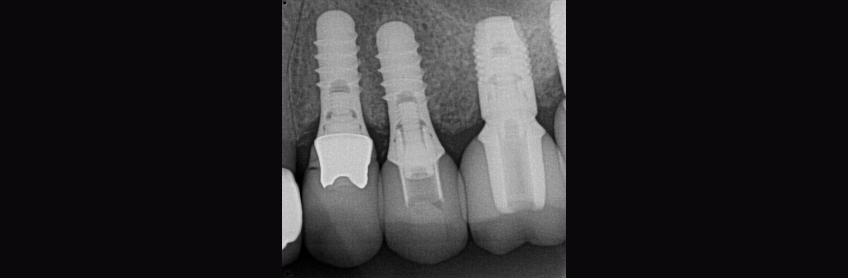

Case Study: Damaged Straumann for an Implant in the #12 Position

The abutment was severely damaged, and the regular Straumann tool couldn’t engage and remove it. Plus, the existing solid abutment would not work as a support or act as retention for the new restoration. So, the question became, what can I do to get the abutment out?

In my case, the shoulder of the implant was not covered, so I could place the RN2 guide on the shoulder and then drill counterclockwise into the solid abutment. Following Straumann’s drilling guidelines, instructions are critical to avoid heating the implant.